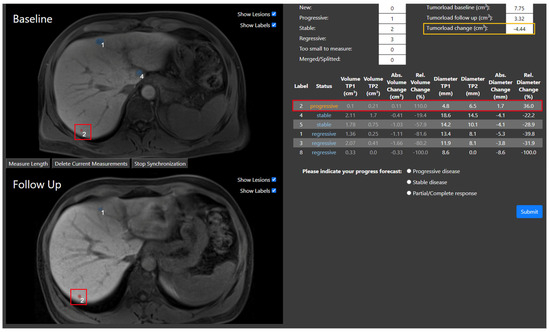

2.3. Evaluation Study

| Progressive | The diameter increased by at least 20% |

| Stable | The diameter change is between 20% increase and 30% decrease |

| Regressive | The diameter decreased by at least 30% |

| New | The lesion only appears in the follow-up MRI |

| Merged | The lesion grew together with another lesion |

| Too small to measure | The lesion has a diameter smaller than 5 mm at both timepoints |

| Metric | Setting 1 | Setting 2 | Setting 3 | p-Value |

|---|---|---|---|---|

| Median decision time in s (IQR) | 13.8 (9.2–21.8) | 14.4 (10.3–24.0) | 23.8 (14.2–42.8) | <0.001 |

| Accuracy in % (SD, range) | 88.7 (SD 11.0, range 67–97) | 90.6 (SD 8.7, range 73–97) | 90.1 (SD 6.1, range 80–97) | 0.72 |

| Precision in % (SD, range) | 81.6 (SD 9.5, range 63–89) | 83.6 (SD 6.4, range 72–89) | 83.4 (SD 5.8, range 73–89) | 0.72 |

| Recall in % (SD, range) | 91.9 (SD 8.7, range 74–98) | 92.9 (SD 7.2, range 78–98) | 90.7 (SD 9.4, range 71–98) | 0.30 |